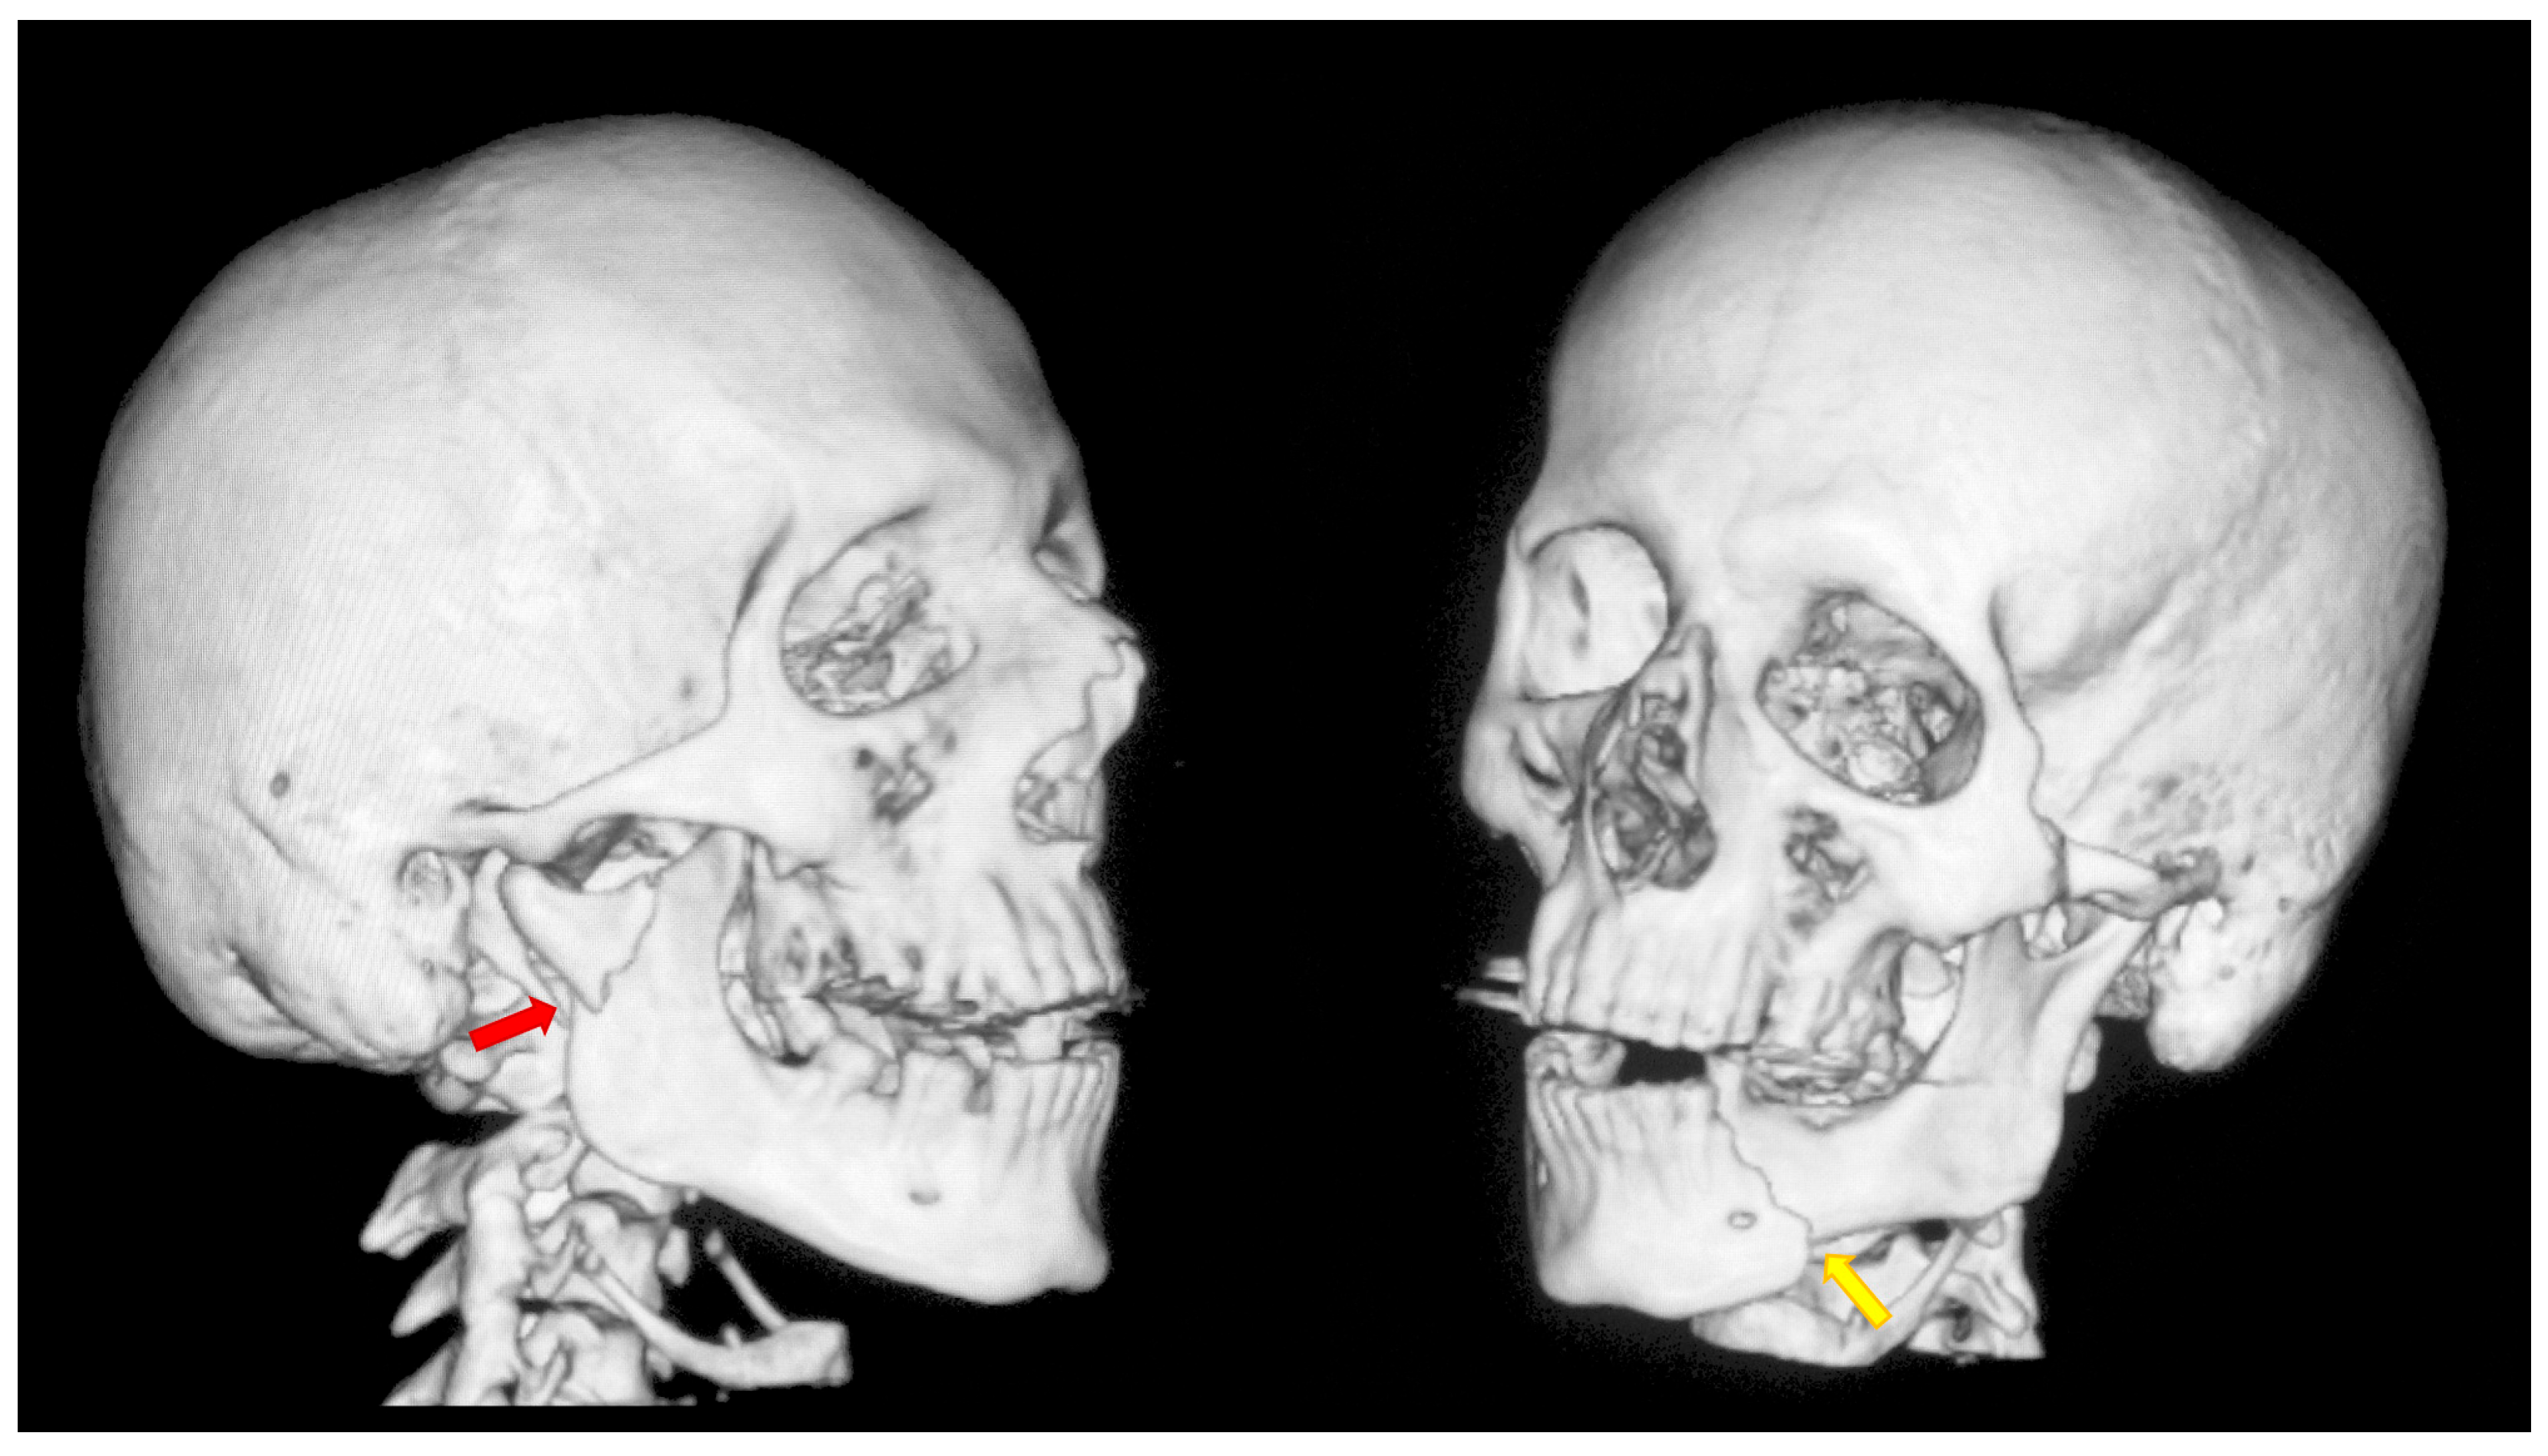

Figure 1.

A typical case of mandibular injury. Computed tomography scan performed prior to treatment. The red arrow indicates a fracture at the base of the mandibular condyle. The yellow arrow indicates an additional fracture in the contralateral mandibular body. This is an epidemiologically typical situation [51]. A fracture of the mandibular condyle very frequently occurs together with another fracture of the mandible. The coexistence of two fracture lines causes significant instability of bone fragments and causes typical malocclusion.